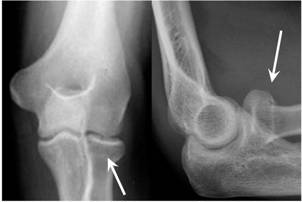

- You have a very small break in the head or neck of the radius bone at your elbow.